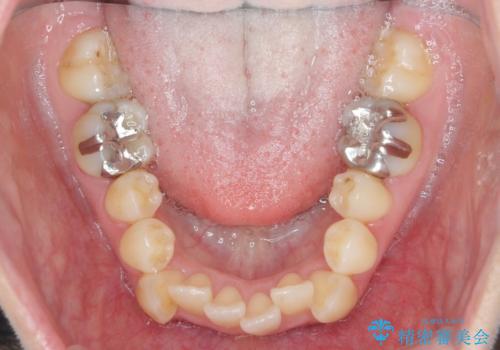

前歯のがたつき すれ違い咬合のマウスピース矯正治療

- 前歯のがたつきや歯の角度、矯正治療を希望され来院されました。

仕事の都合で、ワイヤー矯正を行うことが難しくマウスピース矯正であれば可能、という希望でした。

下顎が前にある咬合関係を可及的に咬合移動で改善し、IPR、下顎3前歯の仕上げで行うマウスピース矯正を計画します。